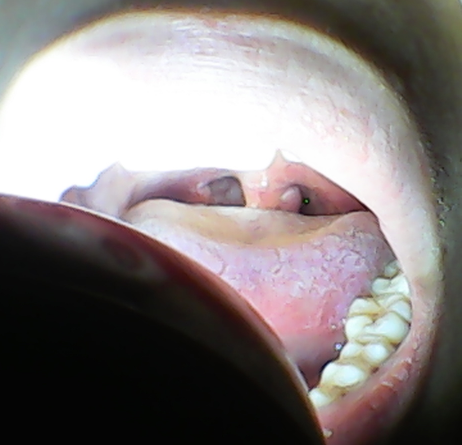

喉咙小舌头有一个球 不疼不痒不影响吃东西 只是咽东西的时候感觉不